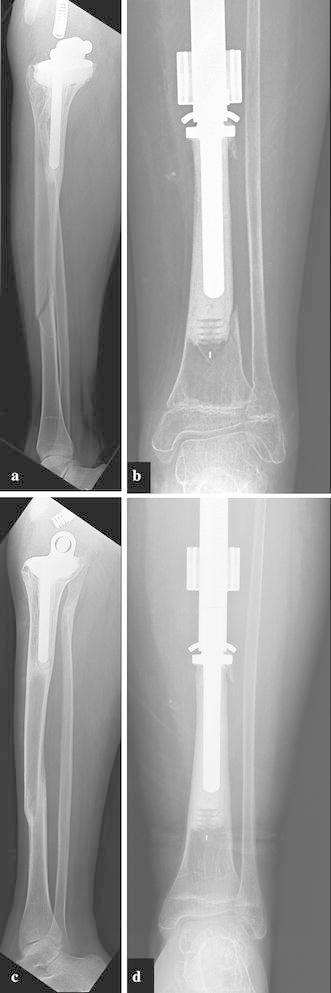

Limb-salvage for primary malignant bone tumors in pediatric patients presents a unique challenge when resection includes an active physis. Early expandable prostheses required open surgical procedures to achieve lengthening. Newer prostheses are capable of achieving expansion without open procedures through the use of an electromagnetic field. This study reports our results with 90 consecutive expansion procedures using the Repiphysis(®) prosthesis. We retrospectively reviewed the records of 20 patients (22 limbs) who underwent limb-salvage using the Repiphysis(®) prosthesis from 2003 to 2015. There were 9 males and 11 females with a mean age of 9 years and 9 months (6-16 years). Reconstruction included the distal femur in 11 cases, total femur in four, proximal tibia in three, proximal humerus in three, and total humerus in one. Complications were reviewed and functional scores were recorded using the MSTS/ISOLS system. Five patients had a second prosthesis implanted during the course of the study for a total of 27 prostheses. The mean follow-up was 57 (6-148) months. Four patients have not been expanded: three due to death prior to lengthening, and one patient who has not yet developed a leg length discrepancy. Ninety consecutive expansion procedures were performed in 18 limbs in 16 patients. A mean of 9 (5-20) mm was gained per expansion and 4.8 cm per patient who has undergone expansion to date. Seven patients have reached skeletal maturity and have been converted to an adult endoprosthesis. These patients averaged 8 expansions per patient and a mean of 7.4 (1.8-12.9) cm in length gained. There were 15 complications in 11 patients including one dislocation, one contracture, four cases of aseptic loosening, five structural failures (three expansion mechanism failures and two tibial fractures), three deep infections, and one case of local recurrence. The mean MSTS score was 80 % (37-97 %) and the limb retention rate was 95 %. The results of this study are comparable to previous studies involving non-invasive prostheses. This study hopefully provides additional data for clinicians to consider when faced with limb threatening sarcomas in the immature skeleton.

对于小儿原发性恶性骨肿瘤进行保肢手术时,如果切除范围包括活跃的生长板,会带来独特的挑战。早期的可扩张假体需要通过开放手术来实现延长。新型假体能够通过使用电磁场在不进行开放手术的情况下实现扩张。本研究报告了我们使用Repiphysis®假体连续进行90次扩张手术的结果。我们回顾性分析了2003年至2015年期间20例(22条肢体)使用Repiphysis®假体进行保肢手术患者的记录。其中男性9例,女性11例,平均年龄为9岁9个月(6 - 16岁)。重建部位包括11例股骨远端、4例全股骨、3例胫骨近端、3例肱骨近端和1例全肱骨。回顾了并发症情况,并使用MSTS/ISOLS系统记录功能评分。5例患者在研究过程中植入了第二个假体,共植入27个假体。平均随访时间为57(6 - 148)个月。4例患者未进行扩张:3例因在延长前死亡,1例尚未出现腿长差异。16例患者的18条肢体共进行了90次连续扩张手术。每次扩张平均增加9(5 - 20)mm,截至目前接受扩张的患者平均每人增加4.8 cm。7例患者已达到骨骼成熟并已转换为成人型假体。这些患者平均每人进行8次扩张,平均增加长度为7.4(1.8 - 12.9)cm。11例患者出现15例并发症,包括1例脱位、1例挛缩、4例无菌性松动、5例结构故障(3例扩张机制故障和2例胫骨骨折)、3例深部感染和1例局部复发。MSTS平均评分为80%(37 - 97%),肢体保留率为95%。本研究结果与先前涉及非侵入性假体的研究结果相当。本研究有望为临床医生在面对未成熟骨骼中威胁肢体的肉瘤时提供更多可供参考的数据。